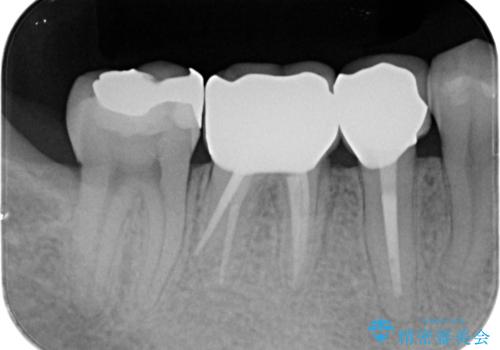

歯周組織が落ち着くのを待ち、セラミッククラウンで機能・審美性を改善します。

歯内・歯周環境が整備されたことで長期的な予後の期待できるセラミック治療を行うことができました。

- 37.4万円(ジルコニアクラウン×2・仮歯×2・歯周外科)費用は治療当時の料金となります